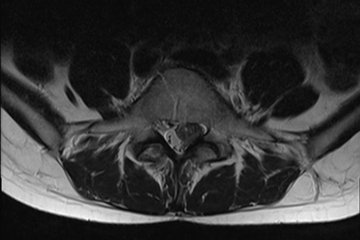

"[...] Von Herzen möchte ich mich bei dem gesamten Team der Benedictus Klinik in Tutzing bedanken. Ohne die Diagnostik und verschiedenen Möglichkeiten der Schmerztherapie wäre es mir heute nicht mehr möglich meinen Beruf, der für mich auch mehr als ein Beruf ist, auszuüben. Durch das gesamte Team, wurden nicht nur sehr schnell meine Bandscheibenvorfälle Diagnostiziert sondern auch die genaue Ursache woran es lag und welche minimal Invasiven Behandlungsmethoden vorhanden sind (wo andere Institutionen mit Sicherheit schon Wirbelsäulenprothesen eingesetzt hätten), sondern mir wurde auch noch sehr schnell und exzellent geholfen. Das gesamte Ärzteteam haben sich viel Zeit genommen, dass was heute am wenigsten verfügbar ist. Sind sehr gut vorbereitet und Organisiert. [...] [Ein super Ärzteteam mit viel Leidenschaft, Menschlichkeit und Beruf als Berufung, sowie die Helferinnen, Schwestern und Verwaltungshelferinnen!]"